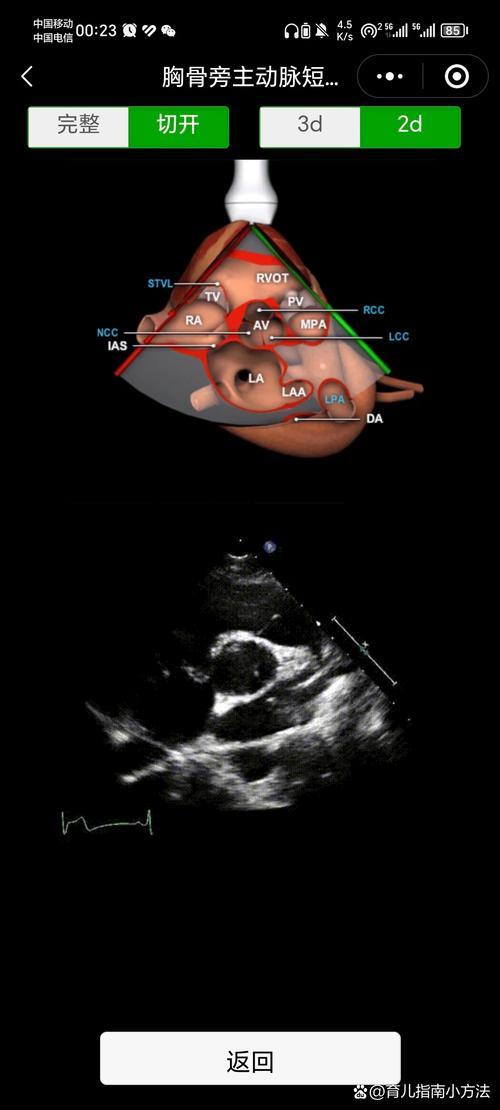

胎儿心脏超声的“九大标准切面”

胎儿心脏超声检查的核心在于获取一系列标准切面,从不同角度观察心脏结构,这九个切面是系统筛查的基础,也是评估任何异常的基石。

| 左心室流出道切面 | 类似于左心室长轴切面 | 观察:左心室流出道、主动脉瓣、主动脉弓的形态和连续性。 |

| 右心室流出道切面 | 类似于右心室流出道长轴切面 | 观察:右心室流出道、肺动脉瓣、主肺动脉的形态和连续性。 |

左/右心室流出道切面 - “出口”检查

- 左心室流出道: 从左心室发出,连接主动脉,主动脉瓣呈“Y”形,开放良好。

- 右心室流出道: 从右心室发出,连接肺动脉,肺动脉瓣呈“一”字形,开放良好。